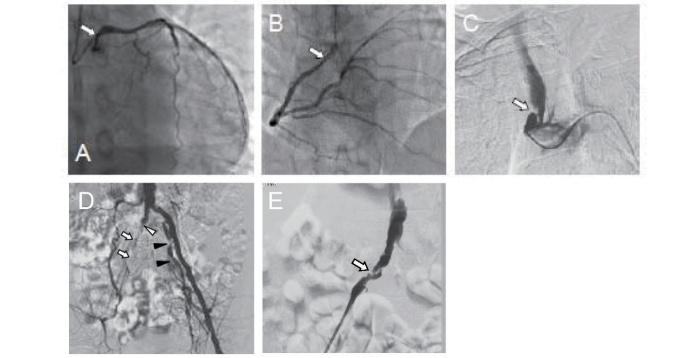

Tangier 病是一种遗传性疾病,其特征是高密度脂蛋白(HDL)-胆固醇(HDL-C)水平极低或完全缺乏。该病由载脂蛋白转运体 A1(ABCA1)基因突变引起,该基因对于细胞内胆固醇和磷脂向 HDL 颗粒的转化至关重要,呈常染色体隐性遗传模式。迄今为止,日本共报道了 35 例 Tangier 病,国外共报道了 109 例。ABCA1 基因两个等位基因突变(纯合子或复合杂合子)的患者,HDL-C 水平通常<5mg/dL,载脂蛋白 A-I(apoA-I)水平<10mg/dL,apoA-I 是 HDL 的主要蛋白成分。Tangier 病患者的主要体征包括:咽扁桃体橘黄色、肝脾肿大、角膜混浊、淋巴结肿大和周围神经病变。尽管患者的 LDL-C 水平通常较低,但仍易发生早发冠心病。目前尚无特效治疗方法,因此早期识别患者并预防动脉粥样硬化的发生至关重要。除了治疗低 HDL-C 外,还应重视 LDL-C 水平、高血压和吸烟等其他危险因素的管理。此外,由于偶尔会出现胰岛β细胞分泌胰岛素受损的情况,因此可能需要治疗葡萄糖耐量异常。